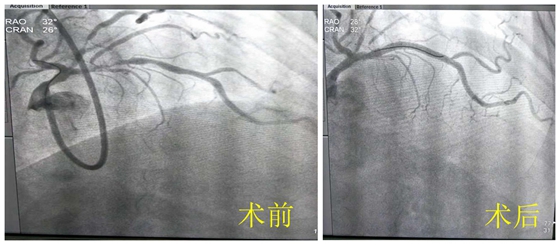

近日,湘雅常德医院心血管内科为一名冠脉严重钙化病变的患者成功实施冠脉旋磨术。 今年63岁的李某,5年前开始反复出现胸闷气促,活动后加重,休息后可逐渐缓解。后因症状逐...